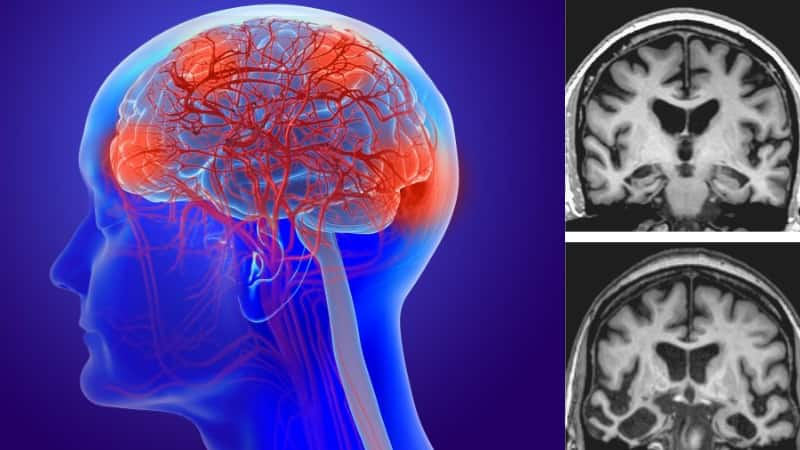

कभी-कभी आपकी बचपन की चोट या आपकी कुछ आदतें आपके लिए और आपके दिमाग के लिए बड़ खतरा बन सकती हैं । और ये आपके सेहत को काफी नुकसान पहुंचा सकती हैं। आपके बचपन की चोट डिमेंशिया बनकर आपके दिमाग को खोखला कर सकती हैं। तो आइए जानते हैं ऐसे कौन से कारक हैं जो आपके दिमाग को कमजोर कर रही हैं।